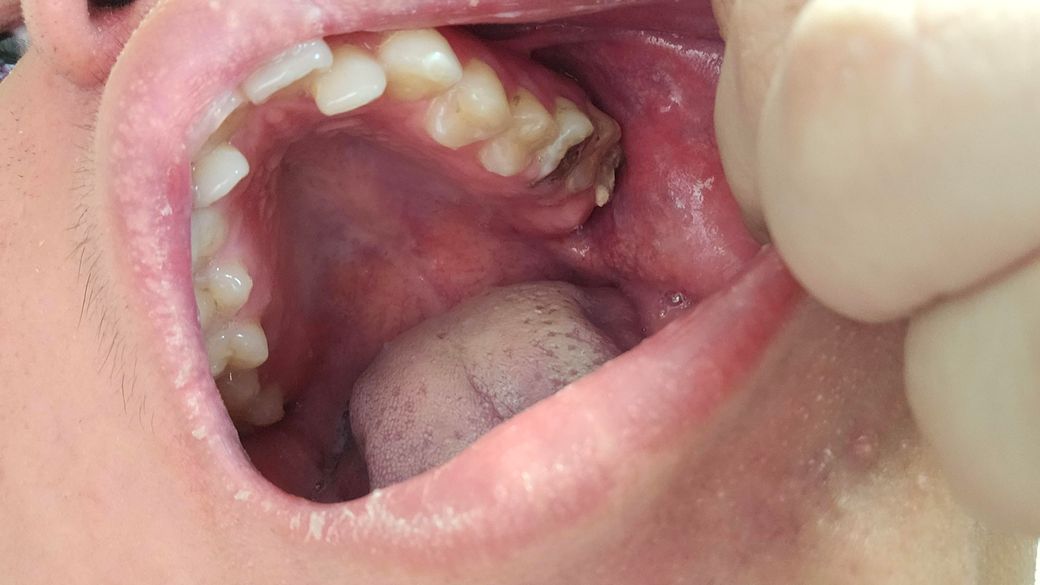

제가 이사진찍히이빨상태 이렇게되는데요 다음주 토요일 갔도 치료할수있나요 알려주세요

• 1번 째 사진

치아 상태가 좋아 보이진 않습니다. 치료는 엑스레이를 찍어보고 치아 상태를 정확히 파악하고 나서 결정해야될것같습니다. 빨리 가셔서 치료를 받아보세요.

사진으로 봤을 경우에는 이미 충치가 많이 진행된것으로 보입니다.

빠른치료가 필요할것으로 보이며 충치가 치아의 뿌리 끝까지 진행이 되었을 경우 발치를 해야 할수 있습니다.

2. 충치가 커서 발치 가능성도 있어보입니다.